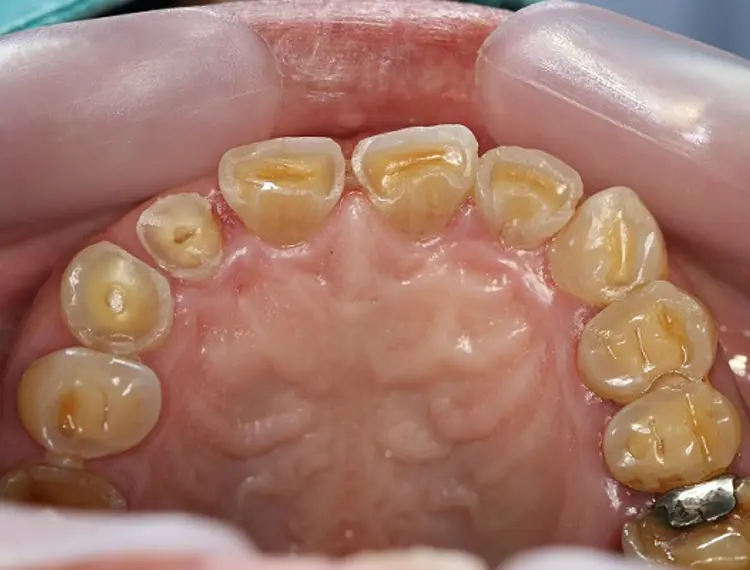

Tooth erosion most commonly occurs on the top, biting surfaces and inside surfaces of teeth. The inside surfaces are particularly affected when the acid comes from reflux and vomiting.

- look shorter with sharp edges

- look darker because the tooth enamel becomes thin, and the yellow dentine can be seen through it